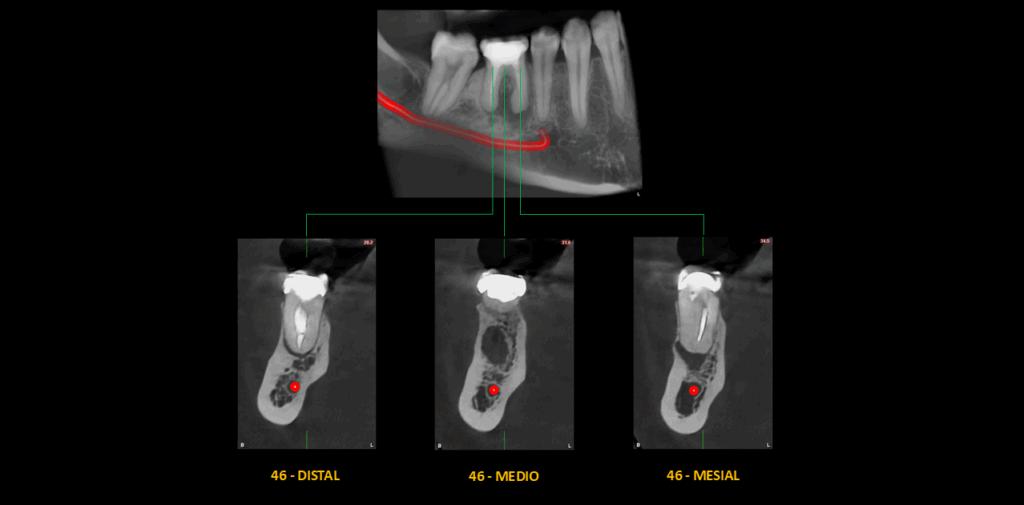

En el estudio complementario mediante tomografía computarizada de haz cónico (TCHC), se confirma que la raíz mesial presenta obturación únicamente del conducto mesiolingual, el cual se encuentra subextendido. El conducto mesiovestibular se visualiza obliterado hasta el tercio medio y atrésico en el tercio apical. El proceso osteolítico periapical presenta morfología curva, con bordes parcialmente corticalizados, y produce adelgazamiento de la tabla ósea vestibular adyacente.

Además, se identifica un patrón de esclerosis ósea circundante, con predominio en el sector distal.